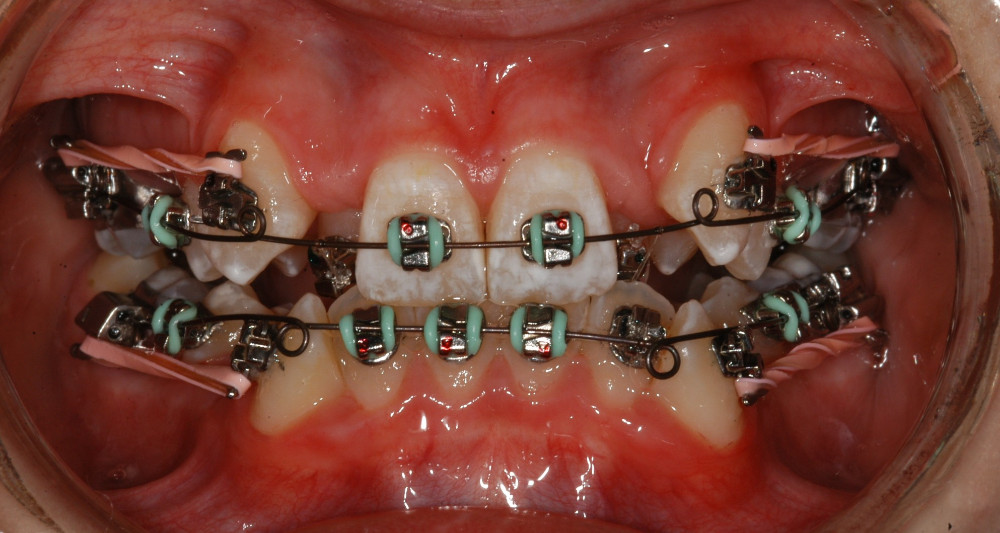

- Tip-Edge PLUS Bracket – Spangen, sichtbare, sehr kleine Metal-Brackets

Das Wichtigste zuerst: Unsere fixe «Plättlispange» funktioniert anders als die meisten anderen fixen Spangen. «TIP-EDGE Plus Orthodontics» ist duch fogenden Eigenschaften gekenntzeichnet:

- ‚Tip-Edge‘ kippt die Zähne anfänglich mit ganz leichten Kräften an ihre richtige Position im Zahnbogen, denn Zähne wollen sich naturgemäs durch Kippen bewegen

- Dazu hängt der Patient nur zwei ganz leichte Elastiks ein – sonst nichts

| Sehr schwere Kiefer-und Zahnfehlstellung Dauer ca. 2-3 Jahre, ev. mit Kieferchirurgie | Metalbrackets | ja | ja | Bild |

| ev. mit Chirurgie in Bern (Lindenhofspital) | Bild |